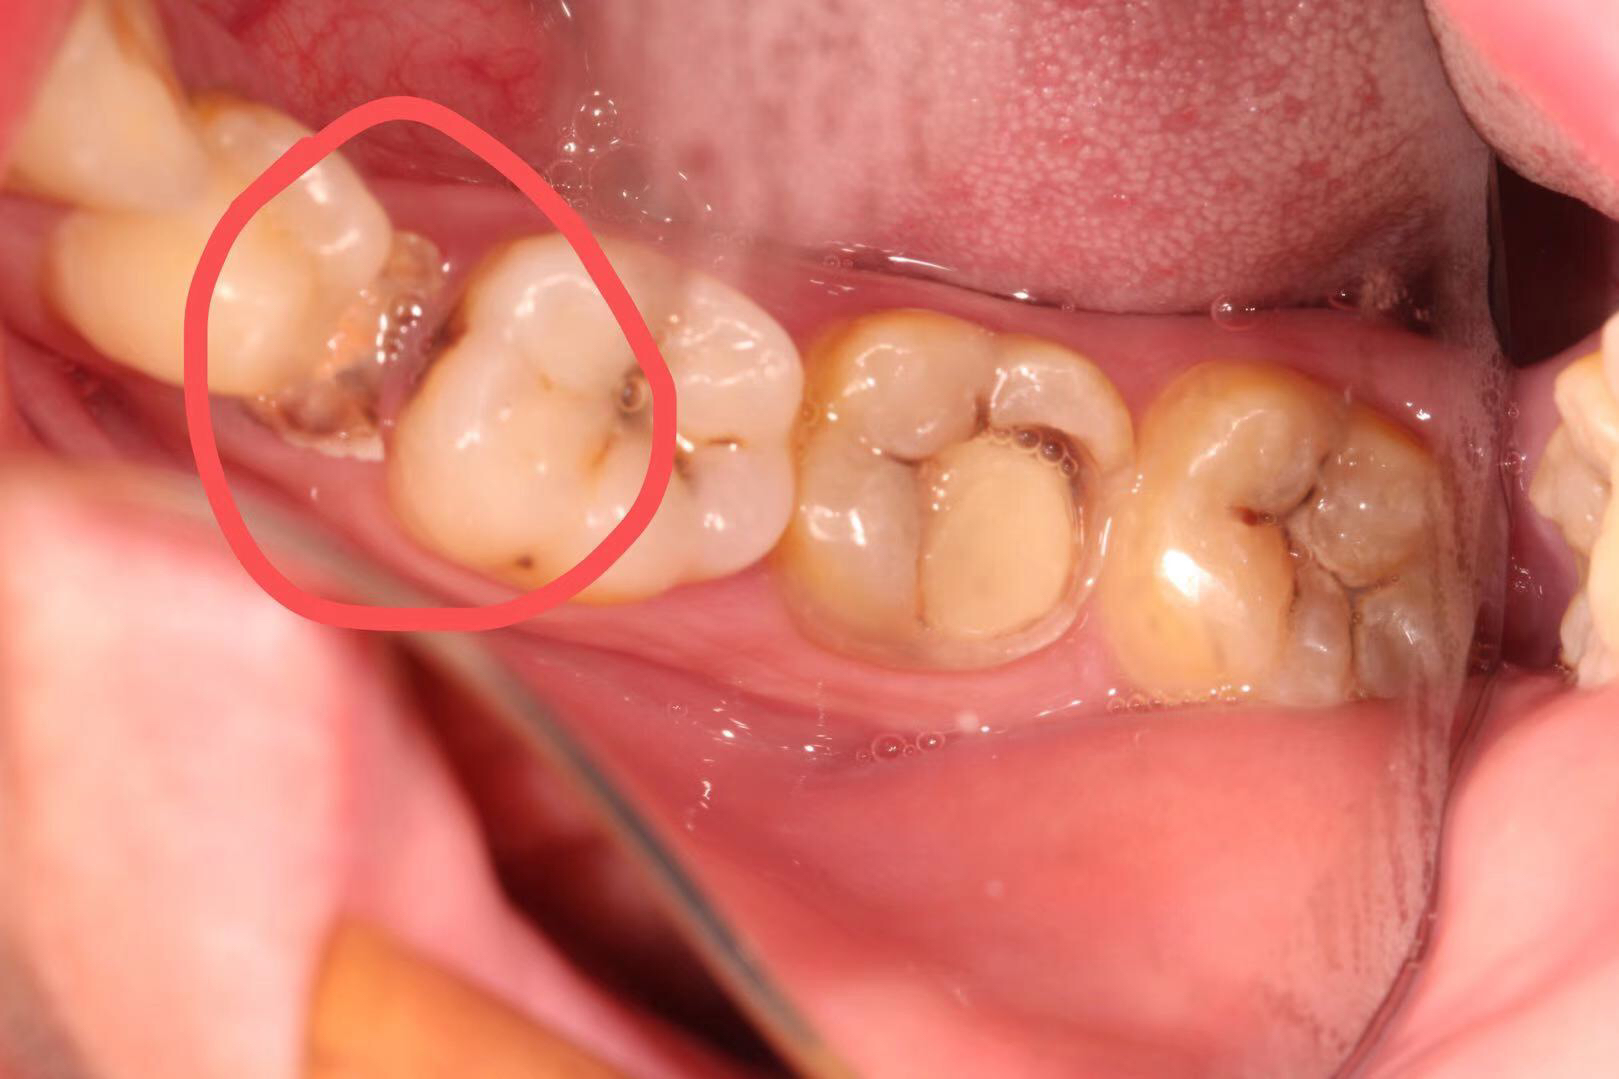

患者是一位刚参加工作的23岁小伙子,右下5号牙由于根管治疗后只是简单补上,没有做高嵌体、全瓷冠等修复方式把牙齿保护起来,吃硬物咬碎且未及时就医,长期腐蚀导致成无法修复的残根,老卢没有采用传统的牙冠桥体修复方式,因为那样对患牙两边的邻牙损伤较大,而是采用老卢最擅长的种植修复,当然老卢做为一名从业20多年的全科医生,其他治疗技术也是不弱的,欢迎牙齿不好的朋友们前来体验。